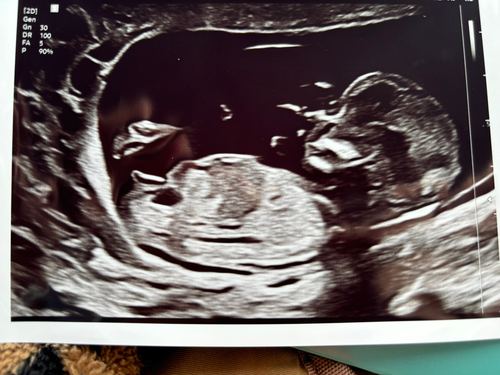

Toch nog een keertje hier. Wat denken jullie?!